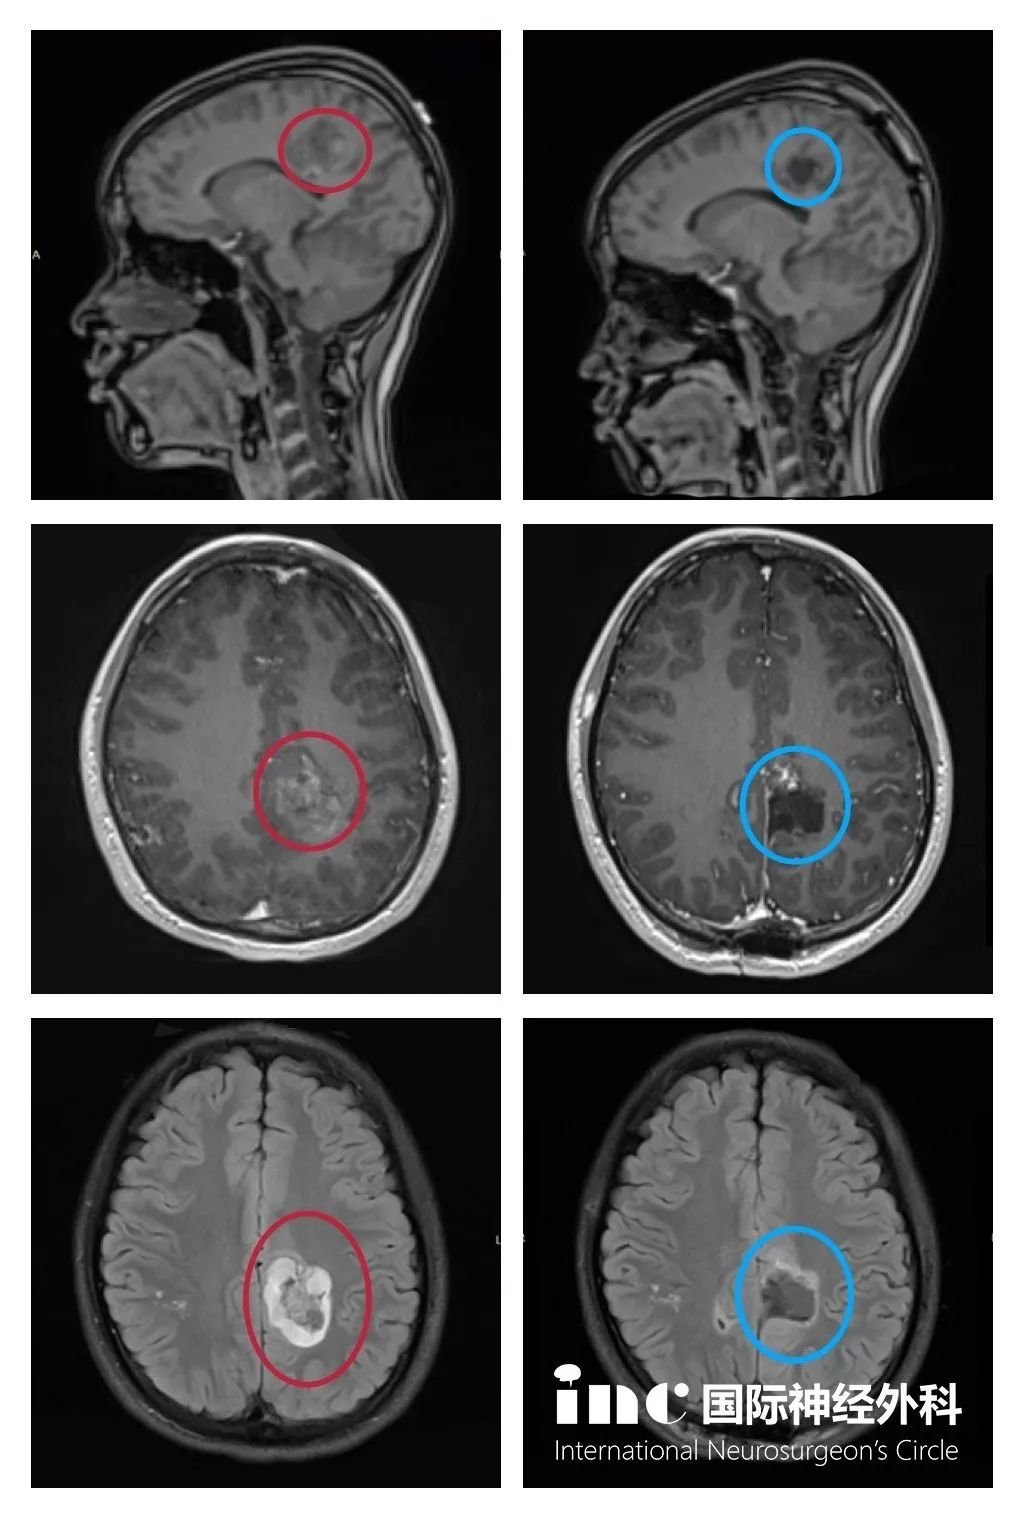

功能區(qū)膠質(zhì)瘤術(shù)前術(shù)后對比

(紅色為術(shù)前,藍(lán)色為術(shù)后)

手術(shù)時間:2020年1月

手術(shù)地點(diǎn):德國INI國際神經(jīng)學(xué)研究所

手術(shù)醫(yī)生:INC德國巴特朗菲教授手術(shù)團(tuán)隊(duì)

術(shù)后情況:手術(shù)后二天出ICU,且能在醫(yī)護(hù)人員攙扶下下地行走,并可以自行持筷用餐。術(shù)后三天,紗布還未拆,患者已能自行下地行走,肢體活動正常,平衡力正常,且沒有其他新癥狀出現(xiàn)。術(shù)后配合醫(yī)院細(xì)致的康復(fù)訓(xùn)練,術(shù)后1周即出院。術(shù)后1個月,孩子恢復(fù)越來越好,沒有癲癇發(fā)作和其他新癥狀出現(xiàn)。